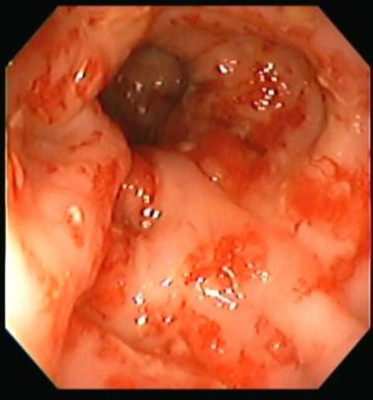

Proctitis

Envíado por Dr. Carlos Ernesto Arévalo